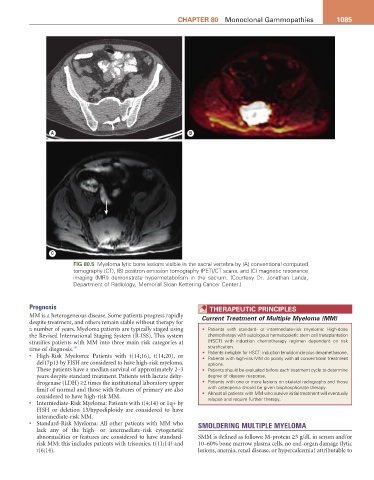

Fig 80.5 Myeloma lytic bone lesions visible in the sacral vertebra by (A) conventional computed

tomography (CT), (B) positron emission tomography (PET)/CT scans, and (C) magnetic resonance

imaging (MRI) demonstrate hypermetabolism in the sacrum. (Courtesy Dr. Jonathan Landa,

Department of Radiology, Memorial Sloan Kettering Cancer Center.)